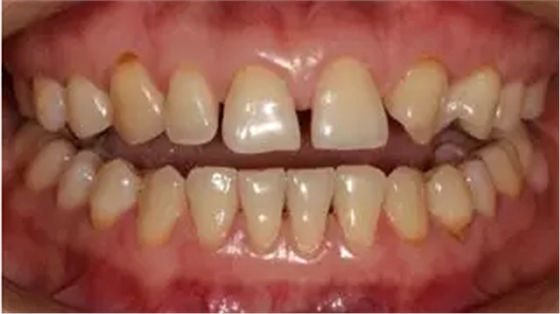

術(shù)前全牙弓咬合照

術(shù)前全牙弓非咬合照

口腔衛(wèi)生尚可,牙齦正常。11,12,21,23 牙體完整,散在間隙,13、24、33、34 頸部楔形缺損,探診無明顯不適,叩(-),無明顯松動(dòng)。冷熱刺激無明顯不適。22 缺失。上下牙咬合穩(wěn)定,覆 覆蓋正常。